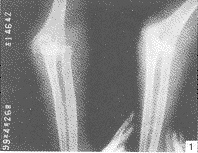

肘关节脱位并尺桡骨远端骨折1例

肘关节脱位|尺骨骨折|桡骨骨折|儿童,关键词:

肘关节脱位;尺骨骨折;桡骨骨折;儿童